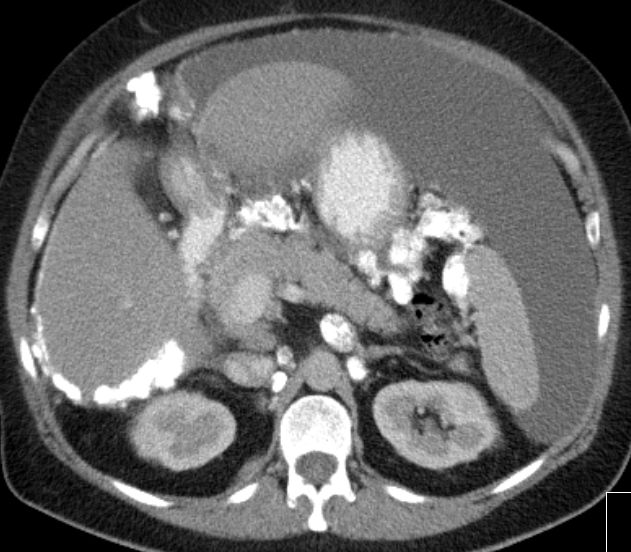

| Fall 2 | 58-jährige Frau mit Adnektektomie beiderseits vor vielen Jahren. Jetzt Peritonealkarzinose mit Verkalkungen. CA 12-5 = 1100, CA 15-3 = 41. Histologie: Proliferate und Infiltraten eines papillär strukturierten Karzinoms. Vergrößerte hyperchromatische Zellkerne. Die mitotische Aktivität ist etwas erhöht. Darstellung von Psammomkörpern. Tumorzellen positiv mit BerEP4, CK 7, WT1 und Östrogenmarker. Kein Nachweis von Calretinin und CK. | |||